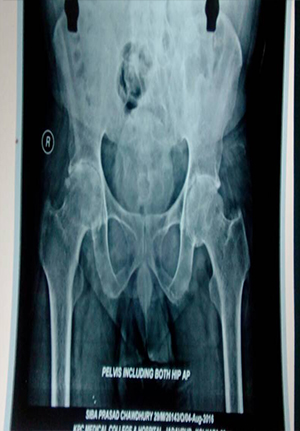

primary total hip replacement in ankylosing hip

preoperative picture of ankylosing hip